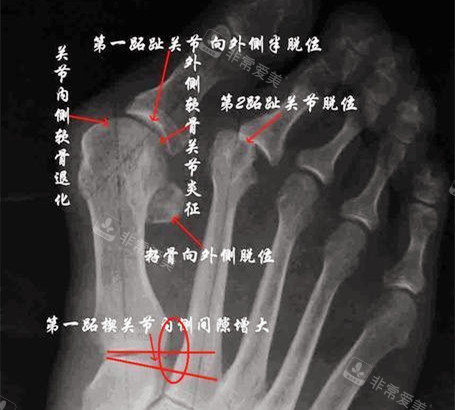

大脚骨外翻程度

苏敬达2026年定价逻辑以拇外翻角(HVA角)跖骨间角(IMA角)为核心测量指标,实现病情与费用的精又准匹配。

重度拇外翻矫正(拇外翻角>40°,跖骨间角>16°伴关节半脱位):60000元左右

大脚骨拍片

大脚骨X光片